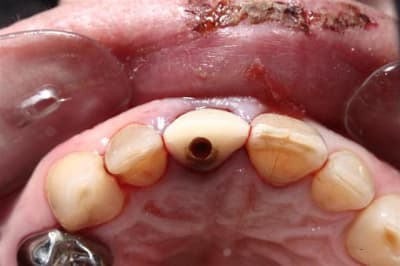

Allez, pour apporter mon caillou à la plage, un cas intéressant, d'implant en urgence.

consultation suite à une chute et fracture de 21 couronnée, un 29 Décembre, décision de poser l'implant le 31.12.

Extraction, mise en place d'un implant de 5*11.5 torque > 35N

Mise en place d'une dent provisoire transvisée.

Prothèse transvisée définitive à 3 mois.

Les 2 dernières photos à 1 an.

la photo ceram en place est à 6 mois. Noter l'amélioration des papilles entre 6 mois et 1 an...